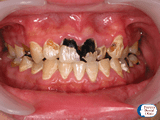

症例2

20代男性。コーラやジュースを毎日大量に飲んでいました。成分に多量に含まれている糖分はバイ菌の栄養になって口腔内で増殖します。また酸性度が高いので本来は水晶に匹敵するくらい丈夫な歯の表面のエナメル質が溶け続けます。悪い状況を続けた結果、ほとんど全ての永久歯がむし歯になってしまいました。まさしく生活習慣病の一つです。このままでは糖尿病やほかの病気も発症してしまい著しく健康を損なうことになります。

欠落していた食生活(食事内容、食事の間隔)の指導、口腔ケアを行っていくことになります。もちろんこの後むし歯の治療をしていきますがたくさんあるので大変です。予防はこうならないために必要なのです。治療にならないようにケアした方がお金や時間がなくならないのでとってもお得です。